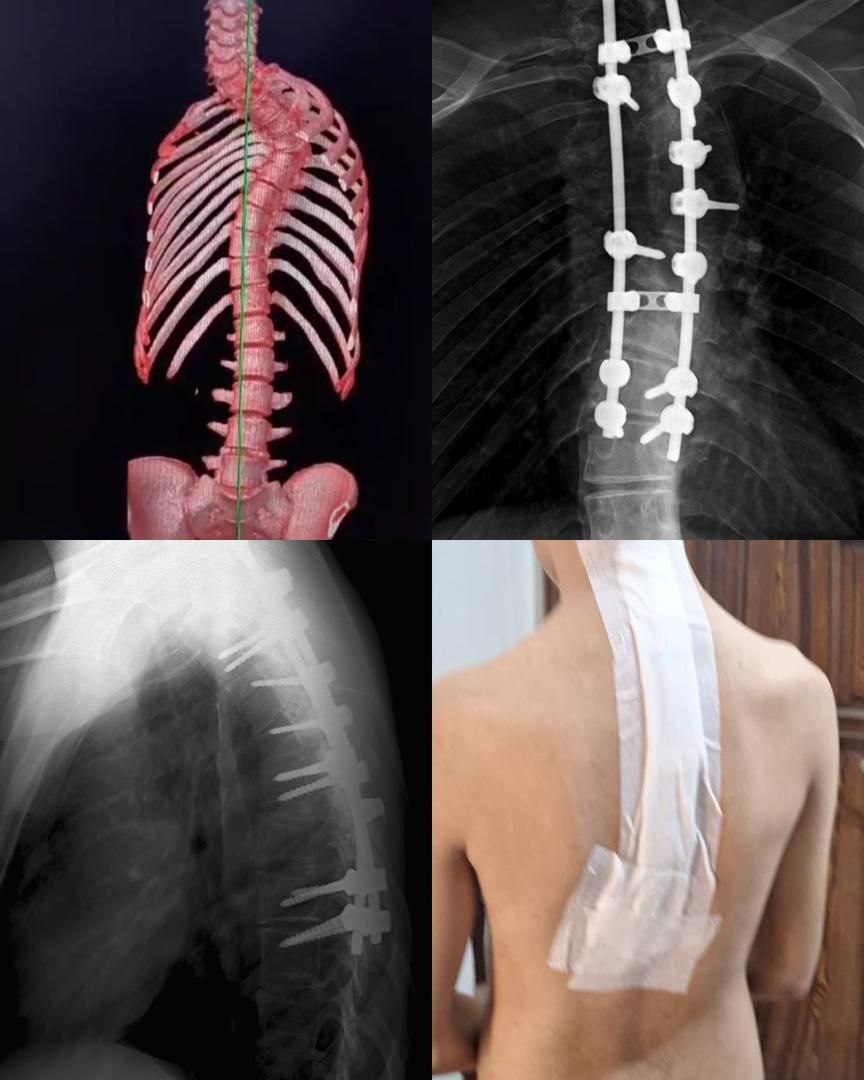

تعديل جنف و حدب

بفضل التعاون المثمر بين شركتنا والدكتور [علي السلوم]، تم تنفيذ عملية تعديل جنف متقدمة باستخدام أحدث تقنيات تثبيت العمود الفقري وبراغي عالية الدقة من شركتنا. النتيجة: تصحيح مثالي للمحور الفقري مع مظهر جراحي أنيق وتقنية تثبيت دقيقة تعكس جودة منتجاتنا وخبرة الطبيب العالية

تعديل جنف

الصورة تُظهر عملية تعديل جنف عند طفل، حيث تم تصحيح انحراف العمود الفقري وتثبيته بواسطة براغٍ وسيخات دقيقة للمحافظة على استقامة الظهر ونمو سليم للعمود الفقري. نُفذت العملية بالتعاون بين شركتنا والدكتور [علي السلوم ] باستخدام أحدث تقنيات التثبيت الطفولي لضمان نتيجة آمنة وجمالية عالية